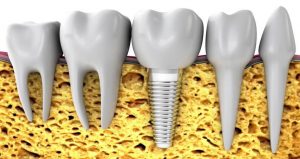

Un implante dental es una raíz artificial de titanio que colocamos en los huesos alveolares de los maxilares, superior o inferior (mandíbula) y que se adapta completamente con los tejidos de la boca. El objetivo y finalidad de los implantes es servir de soporte a una corona o prótesis que sustituirá a piezas dentales que hayamos perdido o que estén muy deterioradas.